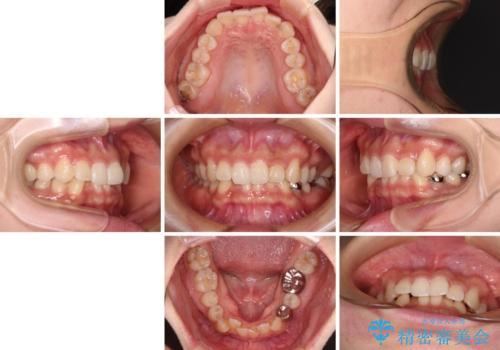

- 前歯のデコボコと深い咬み込みを気にして来院された患者様です。

インビザラインを用いて、前歯の叢生を解消するとともに、深い咬み合わせ(ディープバイト)を改善していくこととしました。

奥歯を後方に直立させることで深い咬み合わせを改善を図り、隠れていた下顎前歯が見えるほどになりました。